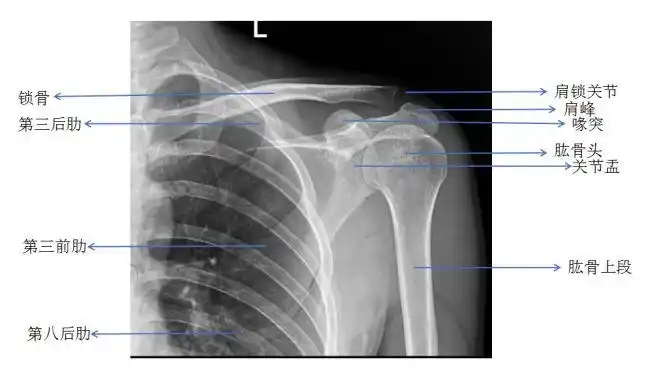

肩关节正位